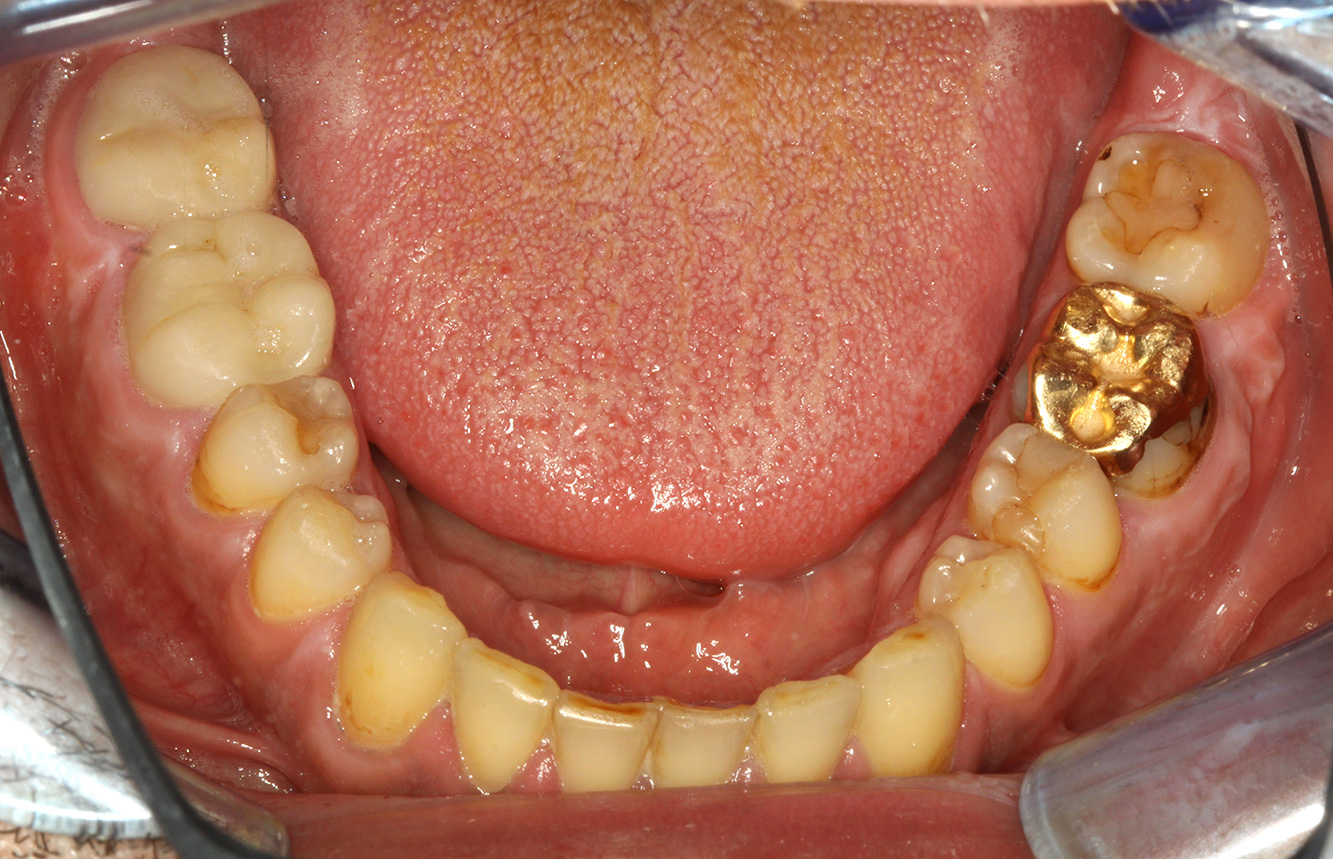

Der Endokarditis-Patient mit aktiven Kariesläsionen*

Der Patient ist 39 Jahre mit Z.n. Herzklappenersatz wegen Klappenfehlers und Endokarditis. Als Antikoagulans (Gerinnungshemmer) wird regelmäßig ASS 100 eingenommen. Aus dem Bereich Lebensstil ist die Ernährungsweise als kariesfördernd einzustufen, da mit hoher Regelmäßigkeit zuckerhaltige Lebensmittel sowie sechs bis sieben Mahlzeiten täglich verzehrt werden. Die Mundgesundheit des Patienten zeigt ein mittleres Kariesrisiko mit aktiven Läsionen. Das Parodontitisrisiko ist niedrig, es besteht eine Gingivitis. Es ergeben sich folgende Empfehlungen für die Prophylaxebehandlung.